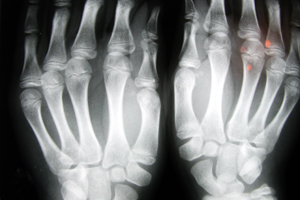

Как уже говорилось выше, патологические изменения возникают сразу во многих участках организма, охватывая различные органы и системы. Заболевание может начаться остро или развиваться десятилетиями и оставаться незамеченным. Часто болезнь начинается постепенно с неярко выраженного воспаления суставов, слабости, утомляемости. При СКВ возможны тяжелые поражения суставов, кожи, нервной системы, почек и других внутренних органов. Изменения носят ревматический характер и затрагивают элементы соединительной ткани. Зачастую встречаются кожные нарушения в виде покраснения и сыпи на скулах и спинке носа, принимающих форму симметричной «волчаночной бабочки». Иногда отмечаются также красные пятна на ногтевых фалангах пальцев. Обычно развивается перикардит, к которому присоединяется миокардит, иногда эндокардит, плеврит, серозный перитонит. Поражение легких приводит к волчаночному пневмониту (кашель, одышка, влажные хрипы в легких). Нередко отмечаются язвенный стоматит, отсутствие аппетита, изжога, отрыжка, увеличение лимфоузлов, печени, селезенки. Бывают и тяжелые поражения нервной системы: энцефалит, полиневрит, судороги, галлюцинации, бредовые состояния. Спектр проявлений на самом деле очень широк.

- Артрит